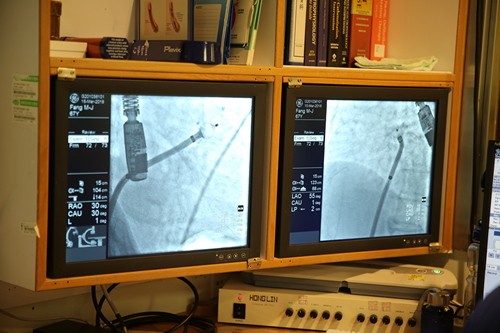

左圖:利用心導管手術把左心耳封阻起來,有效降低心房顫動引起中風的風險,高達九成。

花蓮慈濟醫院近年開始致力於心房顫動的介入治療,心臟內科團隊除了引進冷凍消融儀治療心房顫動外,十五日特地邀請來自香港威爾斯親王醫院的張誠謙醫師(Cheung Shing Him, Gary)指導,與心臟內科蔡文欽醫師、張懷仁醫師為病人進行「左心耳封堵心導管手術」,利用心導管手術把左心耳封阻起來,有效降低心房顫動引起中風的風險,高達九成。

圖說:手術過程中,還有心臟內科主任陳郁志、張懷仁醫師協助經食道超音波提供精準影像以及麻醉團隊的配合,才能完成左心耳封堵心導管術。

為了解決抗凝血問題,「左心耳封堵心導管術」對病人來說是項新選擇。蔡文欽表示,左心耳封堵心導管術約三小時,於患者大腿內側的股靜脈伸入導管,把封堵器從右心房送至左心房,進一步將封堵器植入左心耳。封堵器就像一把降落傘堵塞進左心耳入口,降落傘張開後會與心臟肌肉相連,形成自然屏障,避免血液停留阻滯於左心耳而產生血塊,就能有效降低中風機率。